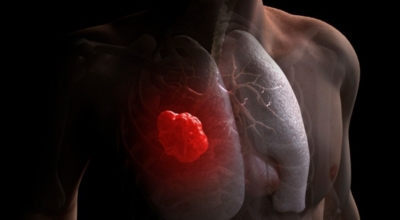

폐암 초기증상 - 흉통

폐암의 초기증상 중에는 흉통이 있답니다. 위치에 따라 요통으로도 진행이 되기도 하는데요 흉통이 발생하는 경우는 폐의 가장자리에 폐암이 발생할 때 나타나게됩니다. 흉막에 암이 인접해 위치하게 되면 바늘로 콕콕 찌르는 듯한 흉통을 느끼게 되며 폐암이 갈비뼈나 다른 부위로도 전이될 경우에도 흉통이 발생하고 요통으로도 발전 할 수 있답니다.